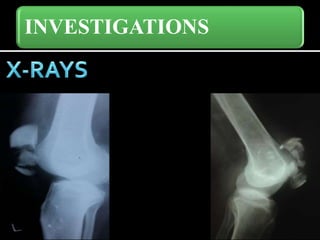

INVESTIGATIONS

• 8.

• 9.